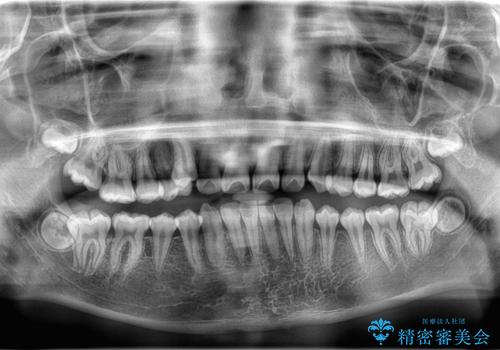

八重歯・歯並びのデコボコとディープバイトを改善した抜歯ワイヤー矯正症例

- 八重歯と咬み合わせを治したいを主訴にご来院された患者様です。

矯正の精密検査の結果上顎左右4番の計2本を抜歯し、審美性に配慮したワイヤー矯正装置(審美装置)を用いて治療を行いました。

八重歯などの歯列のデコボコが綺麗に改善され、患者様にも大変喜んでいただけました。また、咬み合わせが深い「ディープバイト」も併せて改善し、見た目だけでなく機能面でもバランスの取れた咬合を獲得しています。